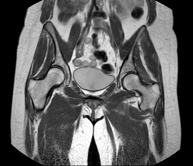

- RM Caderas

Exploración para el estudio de lesiones en tendones, músculos y articulaciones coxofemorales. Permite identificar de forma precoz la artrosis de cadera. Resulta muy útil para detectar las bursitis y la osteopatía dinámica del pubis, frecuente en deportistas. Tiene una duración aproximada de 20 minutos. No emplea radiación ionizante.

- Artro-RM Cadera

Exploración para el estudio de las lesiones en pequeñas estructuras anatómicas de la articulación que suelen lesionarse en pacientes que sufren luxación o pinzamiento (disminución del espacio). El estudio viene precedido por una inyección de contraste en el interior de la articulación, realizada bajo control de rayos X. La duración global de los dos procedimientos es de 50 minutos.